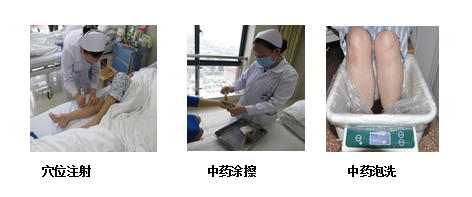

2、中医特色疗法

愈创紫草油作为一种天然制剂,具有明显的抗炎、促进皮肤愈合的作用。通过临应应用观察,使用愈创紫草油治疗的患者,其皮肤反应明显改善,愈合速度加快,生活质量得到了显著提高。

3、运用中医药在放疗减毒增效方面取得显著成效,如通过中药调理减轻放射性炎症、骨髓抑制等副作用,提升患者生存质量。